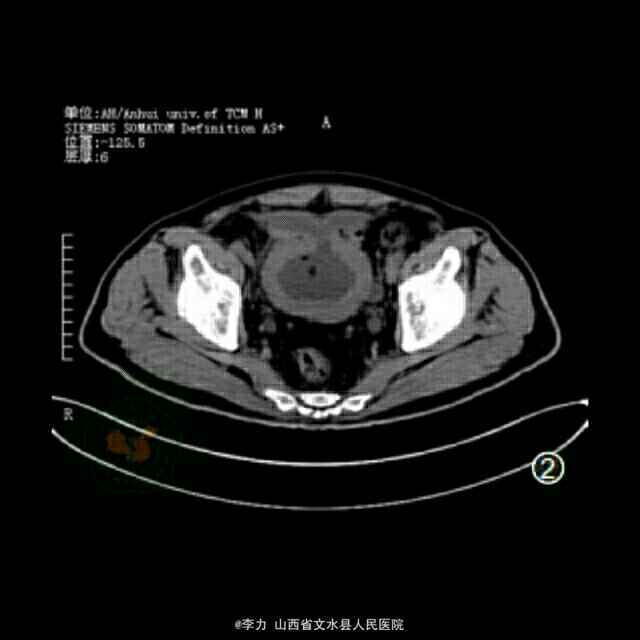

检查超声检查提示双肾轻度积水,膀胱小梁、小房形成,前列腺大小76 mm×72 mm×65mm。盆腔CT平扫显示前列腺重度增生并突入膀胱内(图1)。